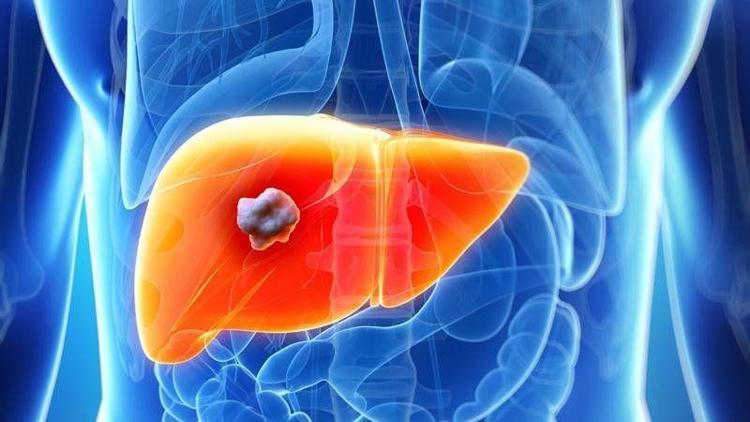

Primer biliyer siroz hastalığı ile 9 yıl mücadele etti. Vücudu eğiten ve bağışıklığı düzelten bir tedavi şekli olan immunoterapi sayesinde hastalığını son bir yılda yenmeyi başardı.

9 yıldır primer biliyer siroz hastalığı ile mücadele eden 51 yaşındaki Selma Şengül’ün yüzü güldü. Bağışıklığı destekleyen ve vücudu eğiten bir tedavi şekli olan immunoterapi ile sağlığına kavuşmayı başardı. Verdiği dokuz yıllık mücadeleyi anlatan Şengül, “2009 yılında primer biliyer siroz tanısı kondu. Hastalığın ilerlemesi engellenemediği için hep araştırma içindeydim. Bir dönem doktorumun tavsiyesi ile bitki kürleri de kullandım. Amerika’daki doktor bir akrabamız hem bitkisel hem de tıbbi tedavi kullanabileceğimi ve orada yaygın olan immunoterapi yöntemini araştırmamı tavsiye etti. Araştırmalarım sonucunda Türkiye’de de bir immunoterapi kliniği olduğunu öğrendim. Bir yıl önce de tedaviye başladım. Diyete çok sıkı bir şekilde uydum tedaviyi hiç aksatmadım. Nitekim son raporumda sirozu tamamen yendiğimi gördüm. Sevinçten üç gün uyumadım. Hayati riski bulunan ve neredeyse yerinden kalkamayan biri için bu bir mucizeydi. Çok tehlikeli bir hastalık, Allah kimseye göstermesin. Hayata daha sıkı bağlandım artık. Emekli olmaya ve çocuklarımla, ailemle daha çok vakit geçirmeye karar verdim. Bol bol geziyoruz, iş yoğunluğundan vakit bulamadığım birçok şeyi artık yapıyorum. Bu hastalık bana hayatın tadını çıkarmam gerektiğini öğretti.

Hastayı değerlendiren ve uygulanan tedavi yöntemine değinen İç Hastalıkları ve İmmunoterapi Uzmanı Dr. Ülkü Görmez, “Bu tedavi tamamen kişiye özel olarak planlanıyor. Kişiyi bizzat inceliyoruz. Altta yatan, otoimmüniteyi tetikleyen bağışıklıktaki sorunları inceliyoruz. Daha sonrasında tanılar koyuyoruz. Bunlar kişiye özel tanılar oluyor. Bundan sonra da onarma tedavisine geçiyoruz. Otoimmünite bağışıklığın kendi kendine saldırısı ile oluşan bir hastalık. Yalnız çok enteresan iki ucu var. Bağışıklıkta otoimmünite hastasının hem bağışıklığının zayıf olduğu noktalar var hem saldırdığı noktalar var. Her iki tarafı da tamir etmeniz gerekiyor. O yüzden de mutlaka doğru tanıların konulması çok önemli. Doğru tanıları koyduktan sonra hasta da uyumluysa işimiz çok kolaylaşıyor. Selma Hanım gerçekten tedavisi süresince çok uyumluydu. Diyetini çok iyi kullandı, ilaçlarını da aynı şekilde, kontrollerini hiç aksatmadı. Dolayısıyla başarılı sonuca ulaştı. Sirozu yendi ama aynı zamanda Sjögren sendromu hastasıydı. Onu da yendi. Gastroentoloji hocamızla da durumunu teyit ettik. Bağırsak florası, bağırsak fonksiyon bozuklukları tamamen normale döndü. Bütün testlerinde çok ciddi düzelmeleri oldu. Çok ciddi yol kat etti. Histamin alerjisini de yendi. Glüten duyarlılığı çok az kaldı. Tedavisinin sonlarına geldik. Bundan sonra sadece bazı özel koruyucu sağlık ve yaşam öneri ile hayatına devam edecek. Ömür boyu immunoterapi almasına gerek yok” şeklinde konuştu.